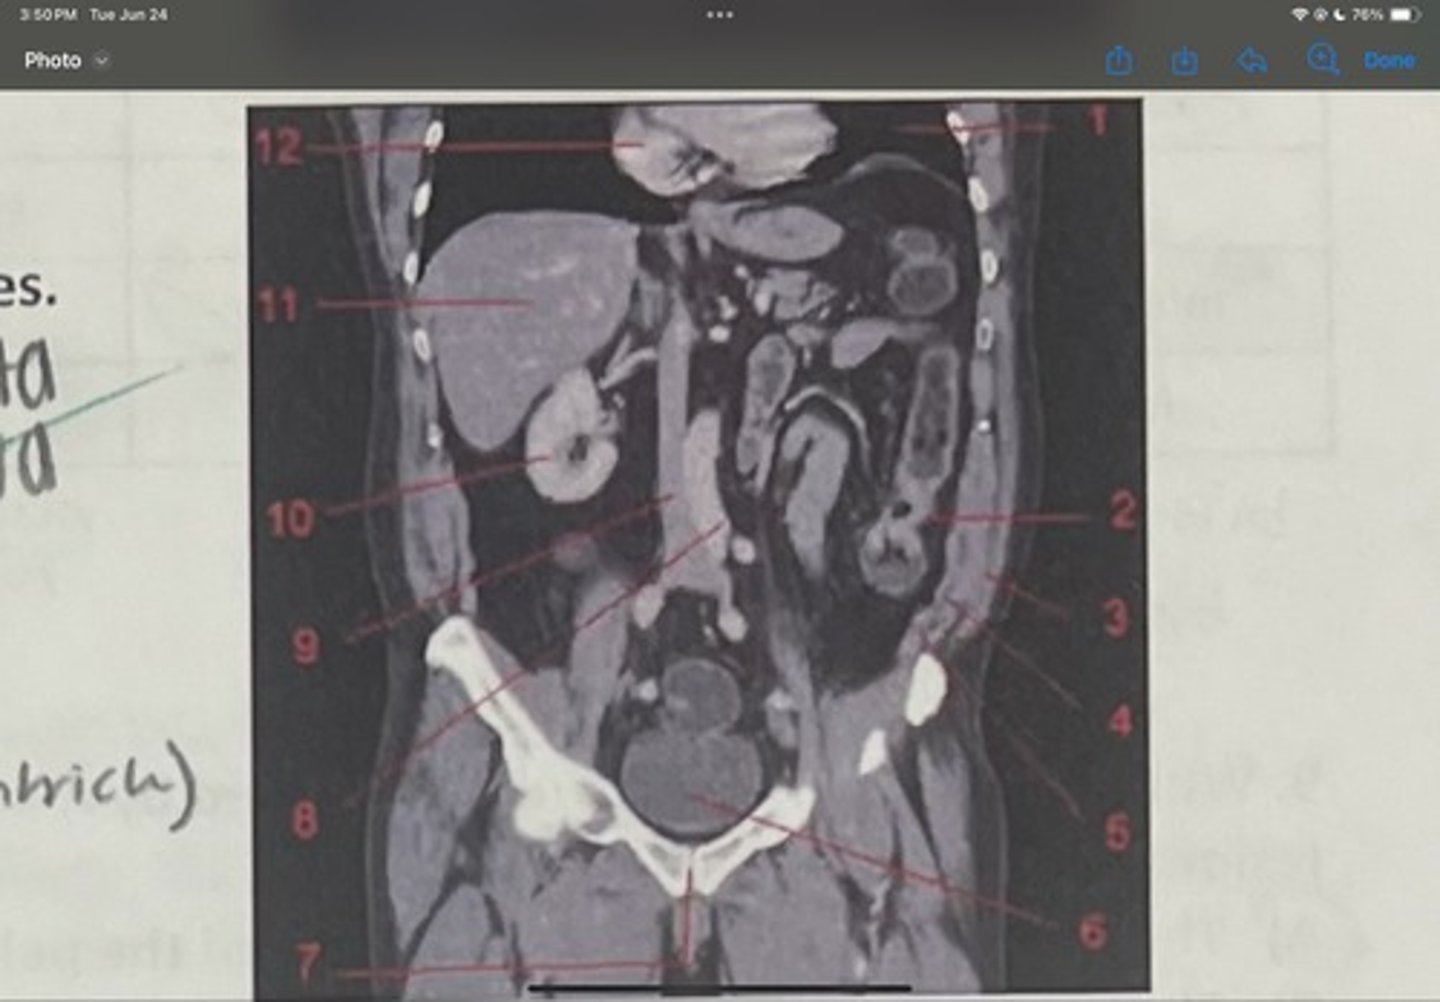

What is 1

Descending colon

What is 2

External oblique

What is 3

Internal obliques

What is 4

Transversus abdominis

What is 5

Bladder

What is 6

Pubic sysmphysis

What is 7

Abdominal aorta

What is 8

Inferior vena cava

What is 9

Right kidney

What is 10

Liver

What is 11

Heart (right ventricle)

What is 12

Subcostal nerve (T12)